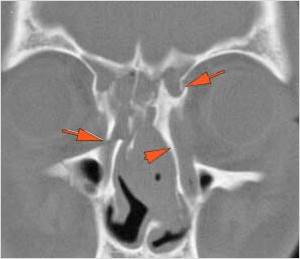

The nasal septum is fractured. [Yes/No]

The nasal bones are fractured. [Yes/No]

The mesial naso-orbito-ethmoid complex is fractured. Specifically, there is bony injury of the nasal bones or the frontal process of the maxilla and the medial walls of the orbit are abnormal. [Yes/No]

The nasolacrimal canal is fractured. [Yes/No]